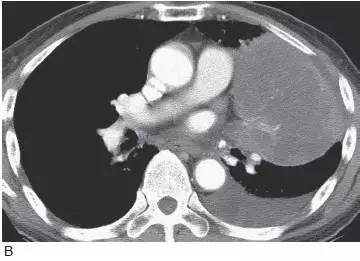

4、小细胞肺癌肺

小细胞肺癌常发生在主支气管或叶支气管,造成广泛的支气管周围侵犯,形成肺门增大或肺门旁肿块( 图10)。支气管腔内肿块较鳞癌少见,但大的肿块常压迫支气管( 图11) 引起肺不张。这种肿瘤常伴有显著的纵隔淋巴结增大( 图12),是引起上腔静脉阻塞综合征的常见原因。少于5%的病例表现为肺结节。

图11 小细胞肺癌

对比增强CT 显示肺门巨大肿块(M),肿瘤包绕并使中间段支气管狭窄( 大箭头),并延伸至隆突下间隙内,局部浸润引起心包增厚( 小箭头),左侧可见胸腔积液